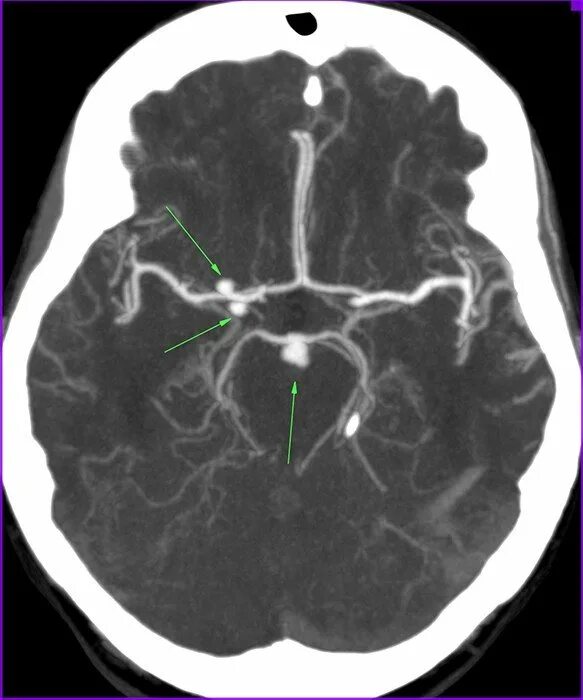

Аневризма головного мозга на кт